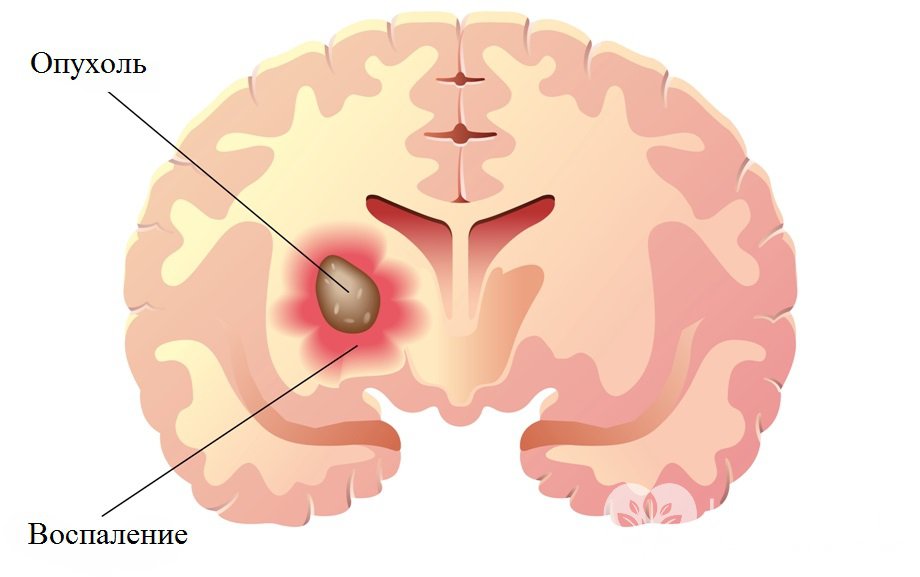

Глиома – наиболее часто встречающаяся первичная опухоль головного мозга, происходящая из клеток нейроглии (вспомогательных клеток нервной ткани).

Глиома – опухоль мозгаСреди всех опухолей головного мозга на долю глиом приходится 60%. Излюбленная локализация – область хиазмы (перекрест зрительных нервов) и стенки желудочков мозга. Значительно реже глиомы локализуются в нервных стволах. Крайне редко наблюдается прорастание глиом в мозговые оболочки, кости черепа.

Глиомы имеют веретенообразную или округлую форму, от 2-4 мм до 10 см в диаметре. Они характеризуются медленным ростом и отсутствием метастазирования, однако при этом способны к выраженному инфильтративному росту, то есть к прорастанию в окружающие ткани. Нередко найти границу между здоровыми тканями и глиомой не удается даже при помощи микроскопа. Еще одной особенностью является развитие дегенеративных процессов в окружающих тканях. В итоге наблюдается несоответствие между выраженностью неврологической симптоматики и размерами глиомы.

По мере роста глиомы приводят к сдавливанию структур головного мозга и повышению внутричерепного давления. Клинически это проявляется возникновением и нарастанием неврологической симптоматики, которая носит стойкий характер.

Глиомы характеризуются медленным ростом и отсутствием метастазирования, однако при этом способны к выраженному инфильтративному росту, то есть к прорастанию в окружающие ткани.